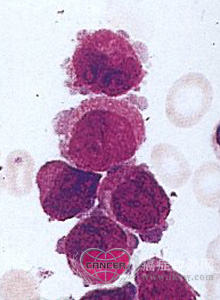

急性原始粒细胞白血病(M1亚型)。骨髓针吸涂片显示原始细胞有一个或多个核仁的常不规则的大核。(a,b)典型的I型原始细胞有松散的打开的染色质,有明确的核仁和没有颗粒的不成熟的胞浆。(c)Ⅱ型原始细胞与I型相似,但有多于15个胞浆细小的嗜天青颗粒,偶尔有Auer小体(箭头)。至少有3%的细胞苏丹黑或髓过氧化物酶染色阳性。